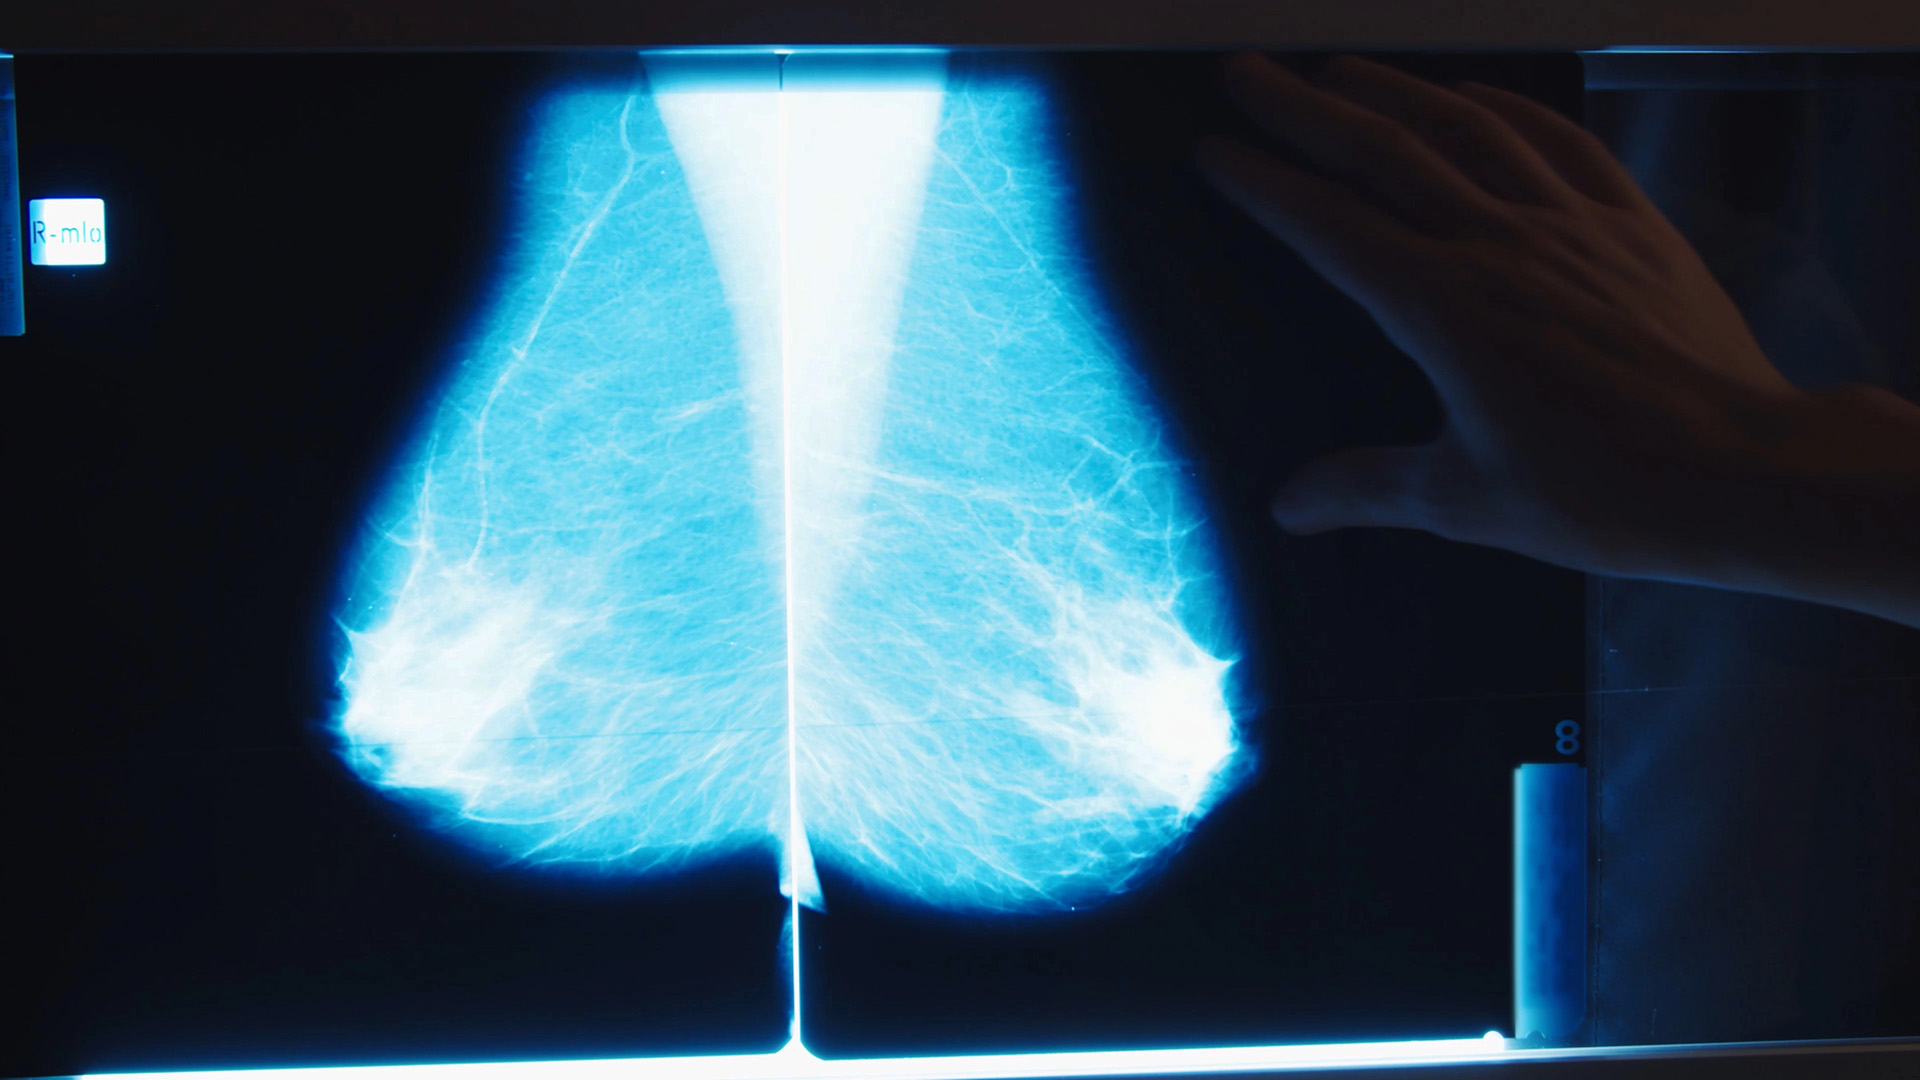

Att vårda kvinnor med bröstcancer

För att ge god vård vid bröstcancer måste personalen ha kunskap om både sina egna reaktioner och om hur kvinnan och hennes anhöriga upplever sjukdomen, skriver Gunvor Ödling i den avhandling hon försvarar vid Umeå universitet den 9 december.

Avhandlingen läggs fram vid Inst. för omvårdnad och har titeln Professional caregivers experiences of caring for women with breast cancer on a surgical ward. Svensk titel: Vårdpersonals erfarenheter av att vårda kvinnor med bröstcancer på en kirurgavdelning.